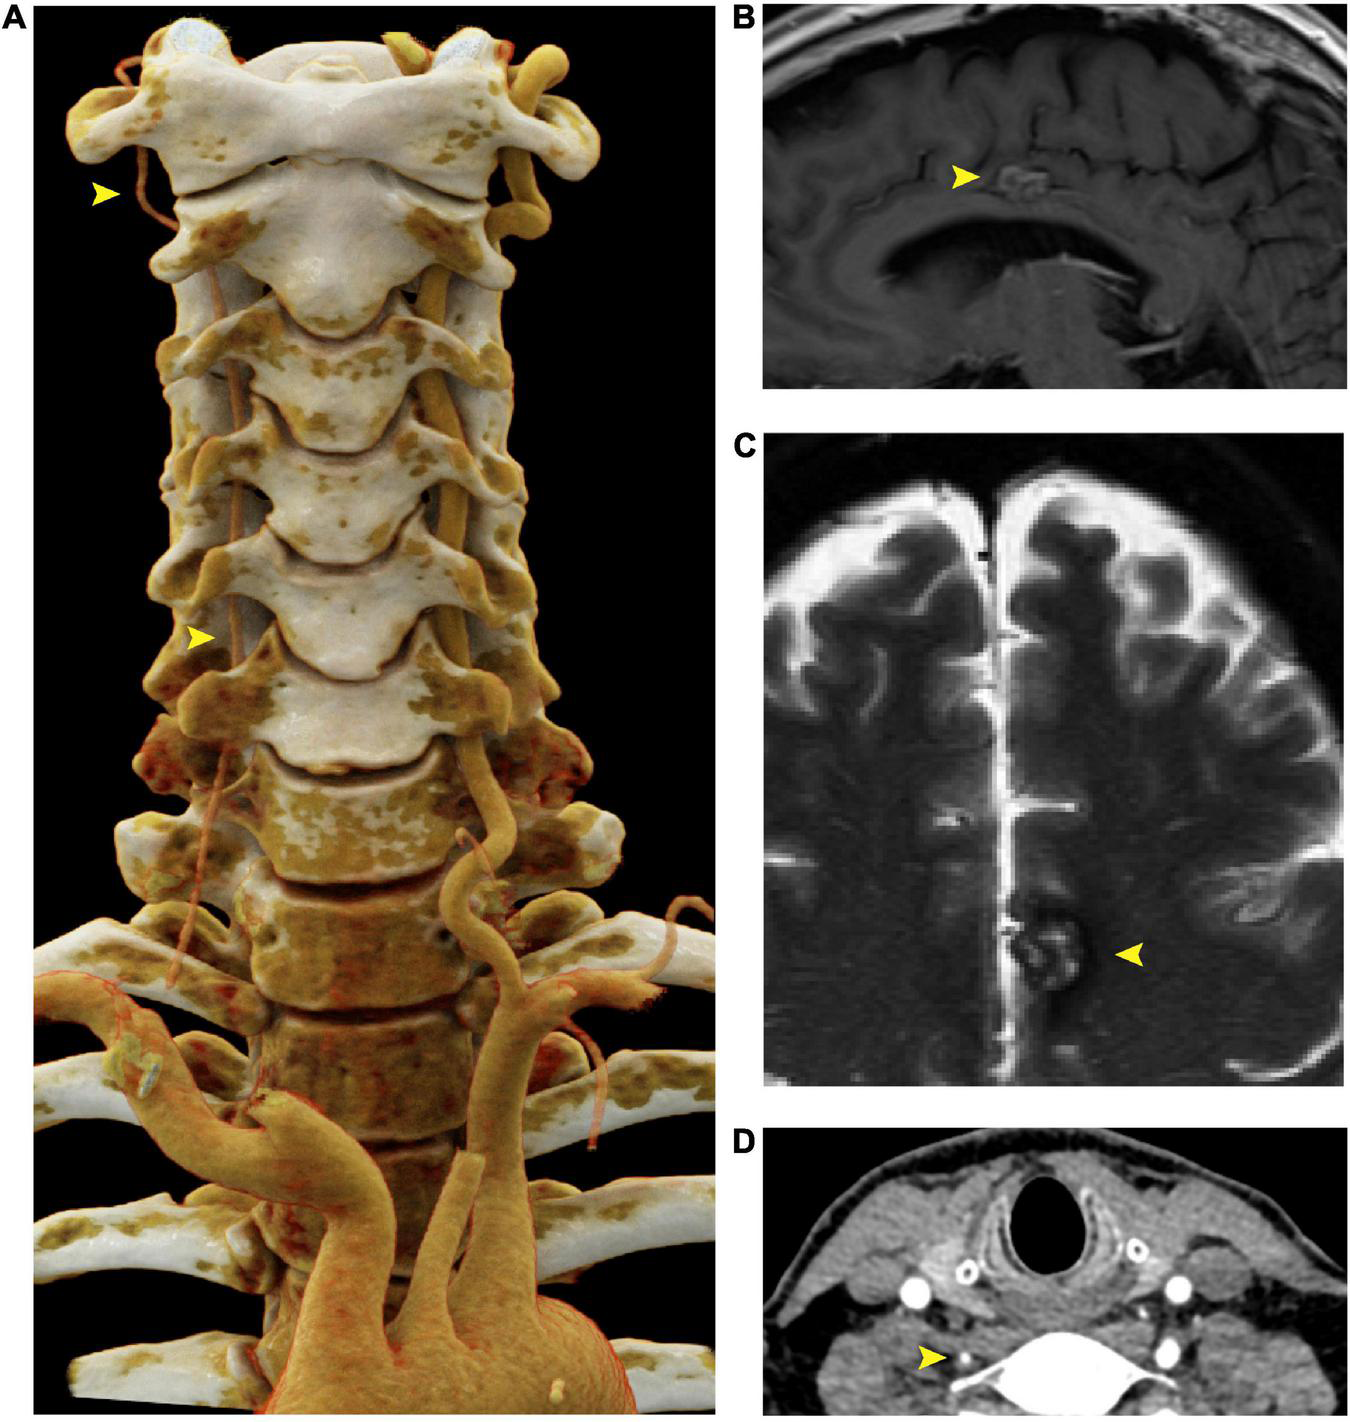

Screening CTA of the head and neck revealed atresia of the right vertebral artery (Figure 2A), but no evidence of intracranial aneurysm. Six months later, the patient underwent magnetic resonance angiography (MRA) of the head, neck, chest, abdomen, and pelvis, which revealed stability of both the thoracic aorta aneurysm (TAA) and AAA as well as mild tortuosity of the external iliac arteries. Incidental findings included a 1.7 cm cavernous malformation in the left cingulate gyrus (Figures 2C, D), which remained stable over the course of six months and continues to be monitored.

FIGURE 2

Right vertebral artery atresia and cavernoma in a 55 year old male harboring a SMAD3 V244F variant. (A) Cinematic 3D reformatted images of the atretic < 2mm right vertebral artery. The origin of the right vertebral artery was sufficiently narrow in caliber that volume averaging resulted in below-threshold density required for visualization in the reformat. For best visualization of the vertebral arteries, the carotid arteries were digitally removed using syngo.via (Siemens, Erlangen). The dominant left vertebral artery measures 5 mm in diameter throughout most of its length, which is the upper limit of normal. (B) Sagittal T1-weighted FLAIR MRI of the brain at the midline shows a cavernous malformation in the left mid cingulate gyrus, just superior to the body of the corpus callosum. (C) Axial T2-weighted MRI with fat saturation demonstrates characteristic signal intensity of cavernous malformation with central hyperintensity, peripheral hypointensity, and susceptibility artifact. (D) Axial CTA demonstrating atretic < 2mm right vertebral artery. FLAIR is fluid-attenuated inversion recovery, MRI is magnetic resonance imaging.